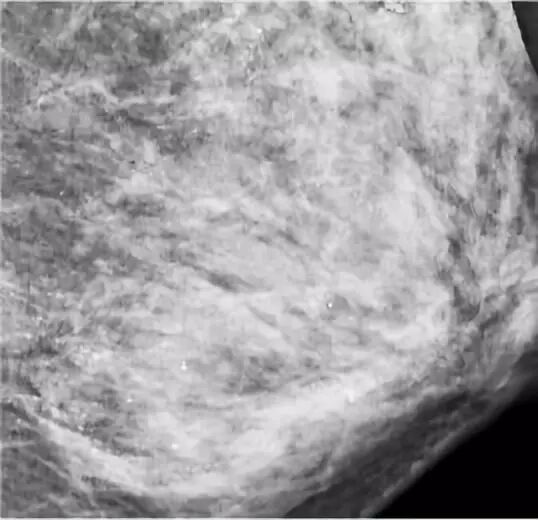

在进行乳腺钼靶X线摄影检查时,医生发现朱女士的左侧乳房布满众多细小如沙子一样、呈散在分布的钙化灶,并且无法轻易判断哪些是良性,哪些是恶性。

钼靶检查发现,朱女士乳腺里满是星星点点的钙化灶 / 武汉晚报